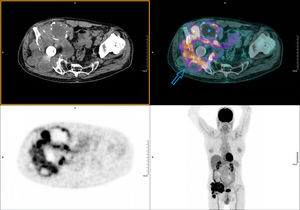

We present the case of a 66-year-old patient, recently diagnosed with bladder carcinoma after a haematuria study, with a picture of lameness and a painless right groin mass, of hard consistency on palpation. As personal background, we highlight a total right hip arthroplasty a few years ago due to severe osteoarthritis. The AP bilateral hip X-ray showed significant bone destruction of the right coxofemoral joint (Fig. 1). In light of these findings, an 18F-FDG PET CT was performed as an extension study of the primary bladder neoformative process, with the possibility of metastatic bone involvement. In the images at 60min post-injection of 18F-FDG a large mass of hypermetabolic multi-lobed soft tissue was observed in the right iliac region, which included the prosthetic material and produced lysis of the iliac wing, with significant destruction of the coxofemoral joint (Fig. 2). A biopsy was performed in view of the findings indicating malignancy, the result was particle disease due to wear and tear of the arthroplasty components. The patient refused surgical revision and is currently undergoing regular follow-up.

PET-CT performed 60min following intravenous administration of 200.14MBq 18F-FDG. Emission and attenuation-corrected images with low-dose CT, from skull vault to upper third of the thighs (whole body protocol). A hypermetabolic mass in the right iliac region, multi-lobed, of approximately 15×13cm and high uptake intensity (SUVmax 14.64). It encompasses the prosthetic material of the hip and extends cranially towards the iliac muscle, causing bone destruction of the iliac wing, the coxofemoral joint and the ischium (arrow). Ametabolic zones are associated indicative of a necrotic/cystic component (star).